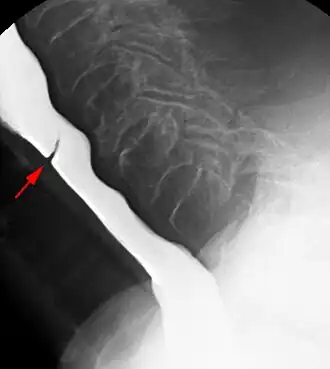

Esophageal web stenosis in barium swallow examination lateral view. -

The diagnostic test of choice is a barium swallow.